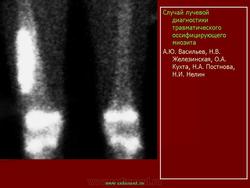

Описывается клинический случай редкого заболевания — оссифицирующего миозита — у девочки 11 лет. Представлены данные литературы, касающиеся этого заболевания.